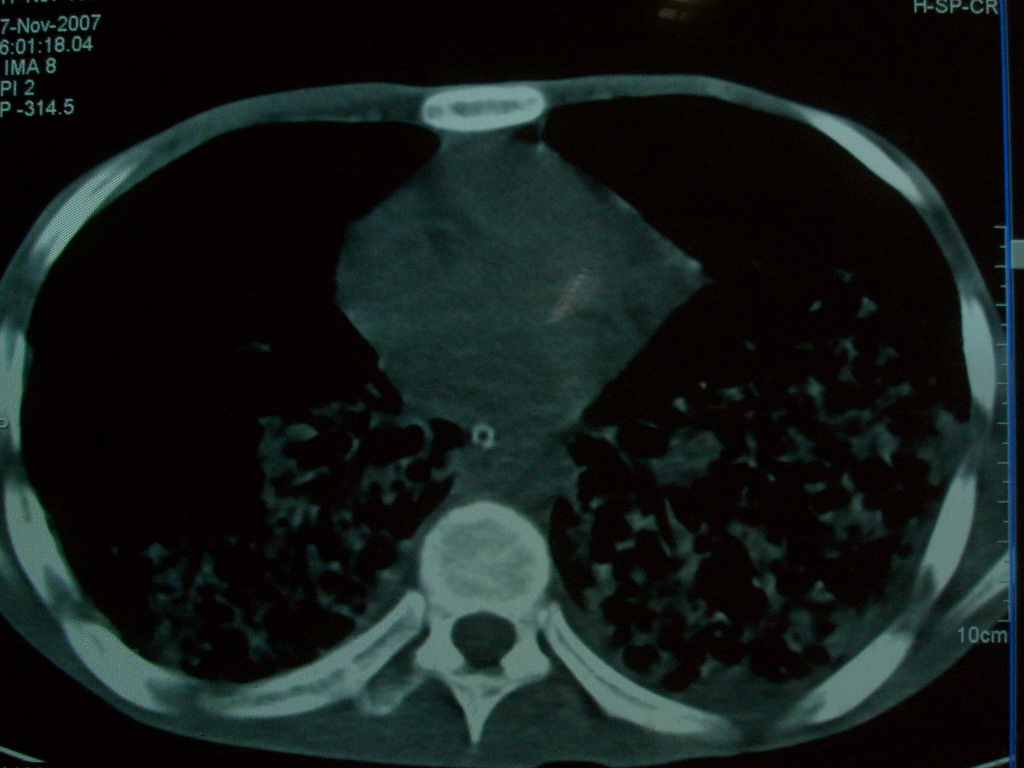

标题: CT10510:男.18岁,咳嗽咳痰两月.(有病理) [打印本页]

标题: CT10510:男.18岁,咳嗽咳痰两月.(有病理)

双肺布满大片状实变及网格状结节影,内参杂大小不等的气囊及空气支气管征,心脏增大。考虑:1 全身结缔组织疾病—系统性红斑狼仓?2 肺泡蛋白沉积症合并感染!

双肺布满大片状实变及网格状结节影,内参杂大小不等的气囊及空气支气管征,双侧胸膜腔少量积液,双下肺近膈面透亮度尚可,病人较年轻,病变较重(不知为什么上胃管?)考虑:1.胶原病肺部改变,2.组织细胞病x。结合实验室检查。

首先考虑组织细胞x病。两肺中上肺野多发囊腔,中下肺野内见多发小结节,并可见肺间质增厚。患者是男性,年龄较小。胶原性病变比较多见的类风湿、系统性红斑狼疮和硬皮病临床和影像均不是很支持,类风湿和系统性红斑狼疮的肺部表现最常见的是胸腔积液,硬皮病可见食管的扩张。

肺内多发斑片状、结节状、融合大片状及网格状影,多发薄壁空腔影,胸膜肥厚,纵隔、气管右移,考虑ⅲ型肺结核,多发空洞,继发肺间质纤维化。

双肺结核并播散.患者以肠梗阻入院,手术为肠结核.术后咳嗽做ct检查.